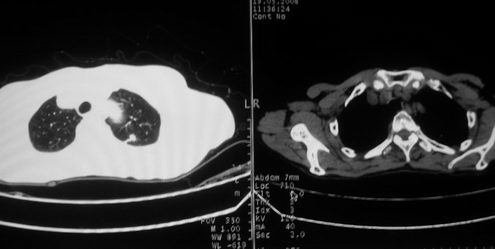

以下是引用zjzjr在2008-5-19 13:40:00的发言:[br]支持左上肺周围型肺癌(腺癌可能性大)伴颅内多发性转移.